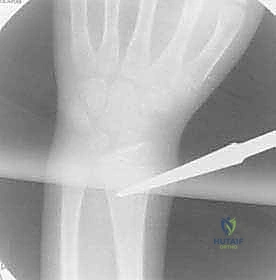

الدليل الجراحي التفصيلي: خطوة بخطوة مع الأستاذ الدكتور محمد هطيف

لإبراز المستوى المتقدم من الرعاية الطبية، نستعرض هنا الخطوات الدقيقة التي يتبعها الأستاذ الدكتور محمد هطيف وفريقه الجراحي في غرفة العمليات المجهزة بأحدث التقنيات.

تُجرى العملية تحت التخدير العام لضمان راحة الطفل التامة. يتم تعقيم الذراع بالكامل وتغطيتها بالستائر الجراحية المعقمة. يُستخدم جهاز الأشعة السينية المتحرك (Fluoroscopy / C-arm) طوال العملية لتوجيه الجراح بدقة.

3. فتح المداخل الجراحية (Incision)

يتميز الدكتور هطيف بإجراء شقوق جراحية تجميلية دقيقة لا تتجاوز 2 سم:

* لعظم الكعبرة: يتم عمل شق صغير بالقرب من الرسغ (فوق الكردوس البعيد للكعبرة) مع حماية فائقة للفرع الحسي للعصب الكعبري.

* لعظم الزند: يتم عمل شق صغير بالقرب من الكوع (تحت الناتئ الزجي).

4. فتح القناة النخاعية

باستخدام أداة دقيقة (Awl)، يقوم الدكتور هطيف باختراق قشرة العظم لإنشاء نقطة دخول للمسمار، مع الحرص الشديد على عدم إيذاء صفيحة النمو القريبة.

5. إدخال المسمار المرن

يتم إدخال المسمار المرن (المثني مسبقاً)